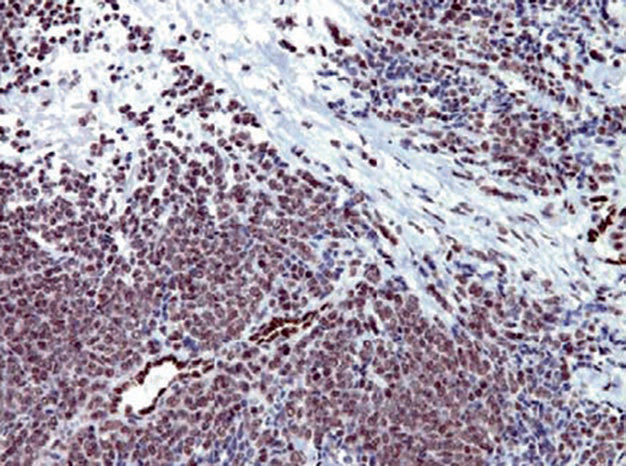

图2. Ewing肉瘤,FLI-1在细胞核呈强阳性表达;注意,图中血管内皮细胞可作为内对照。